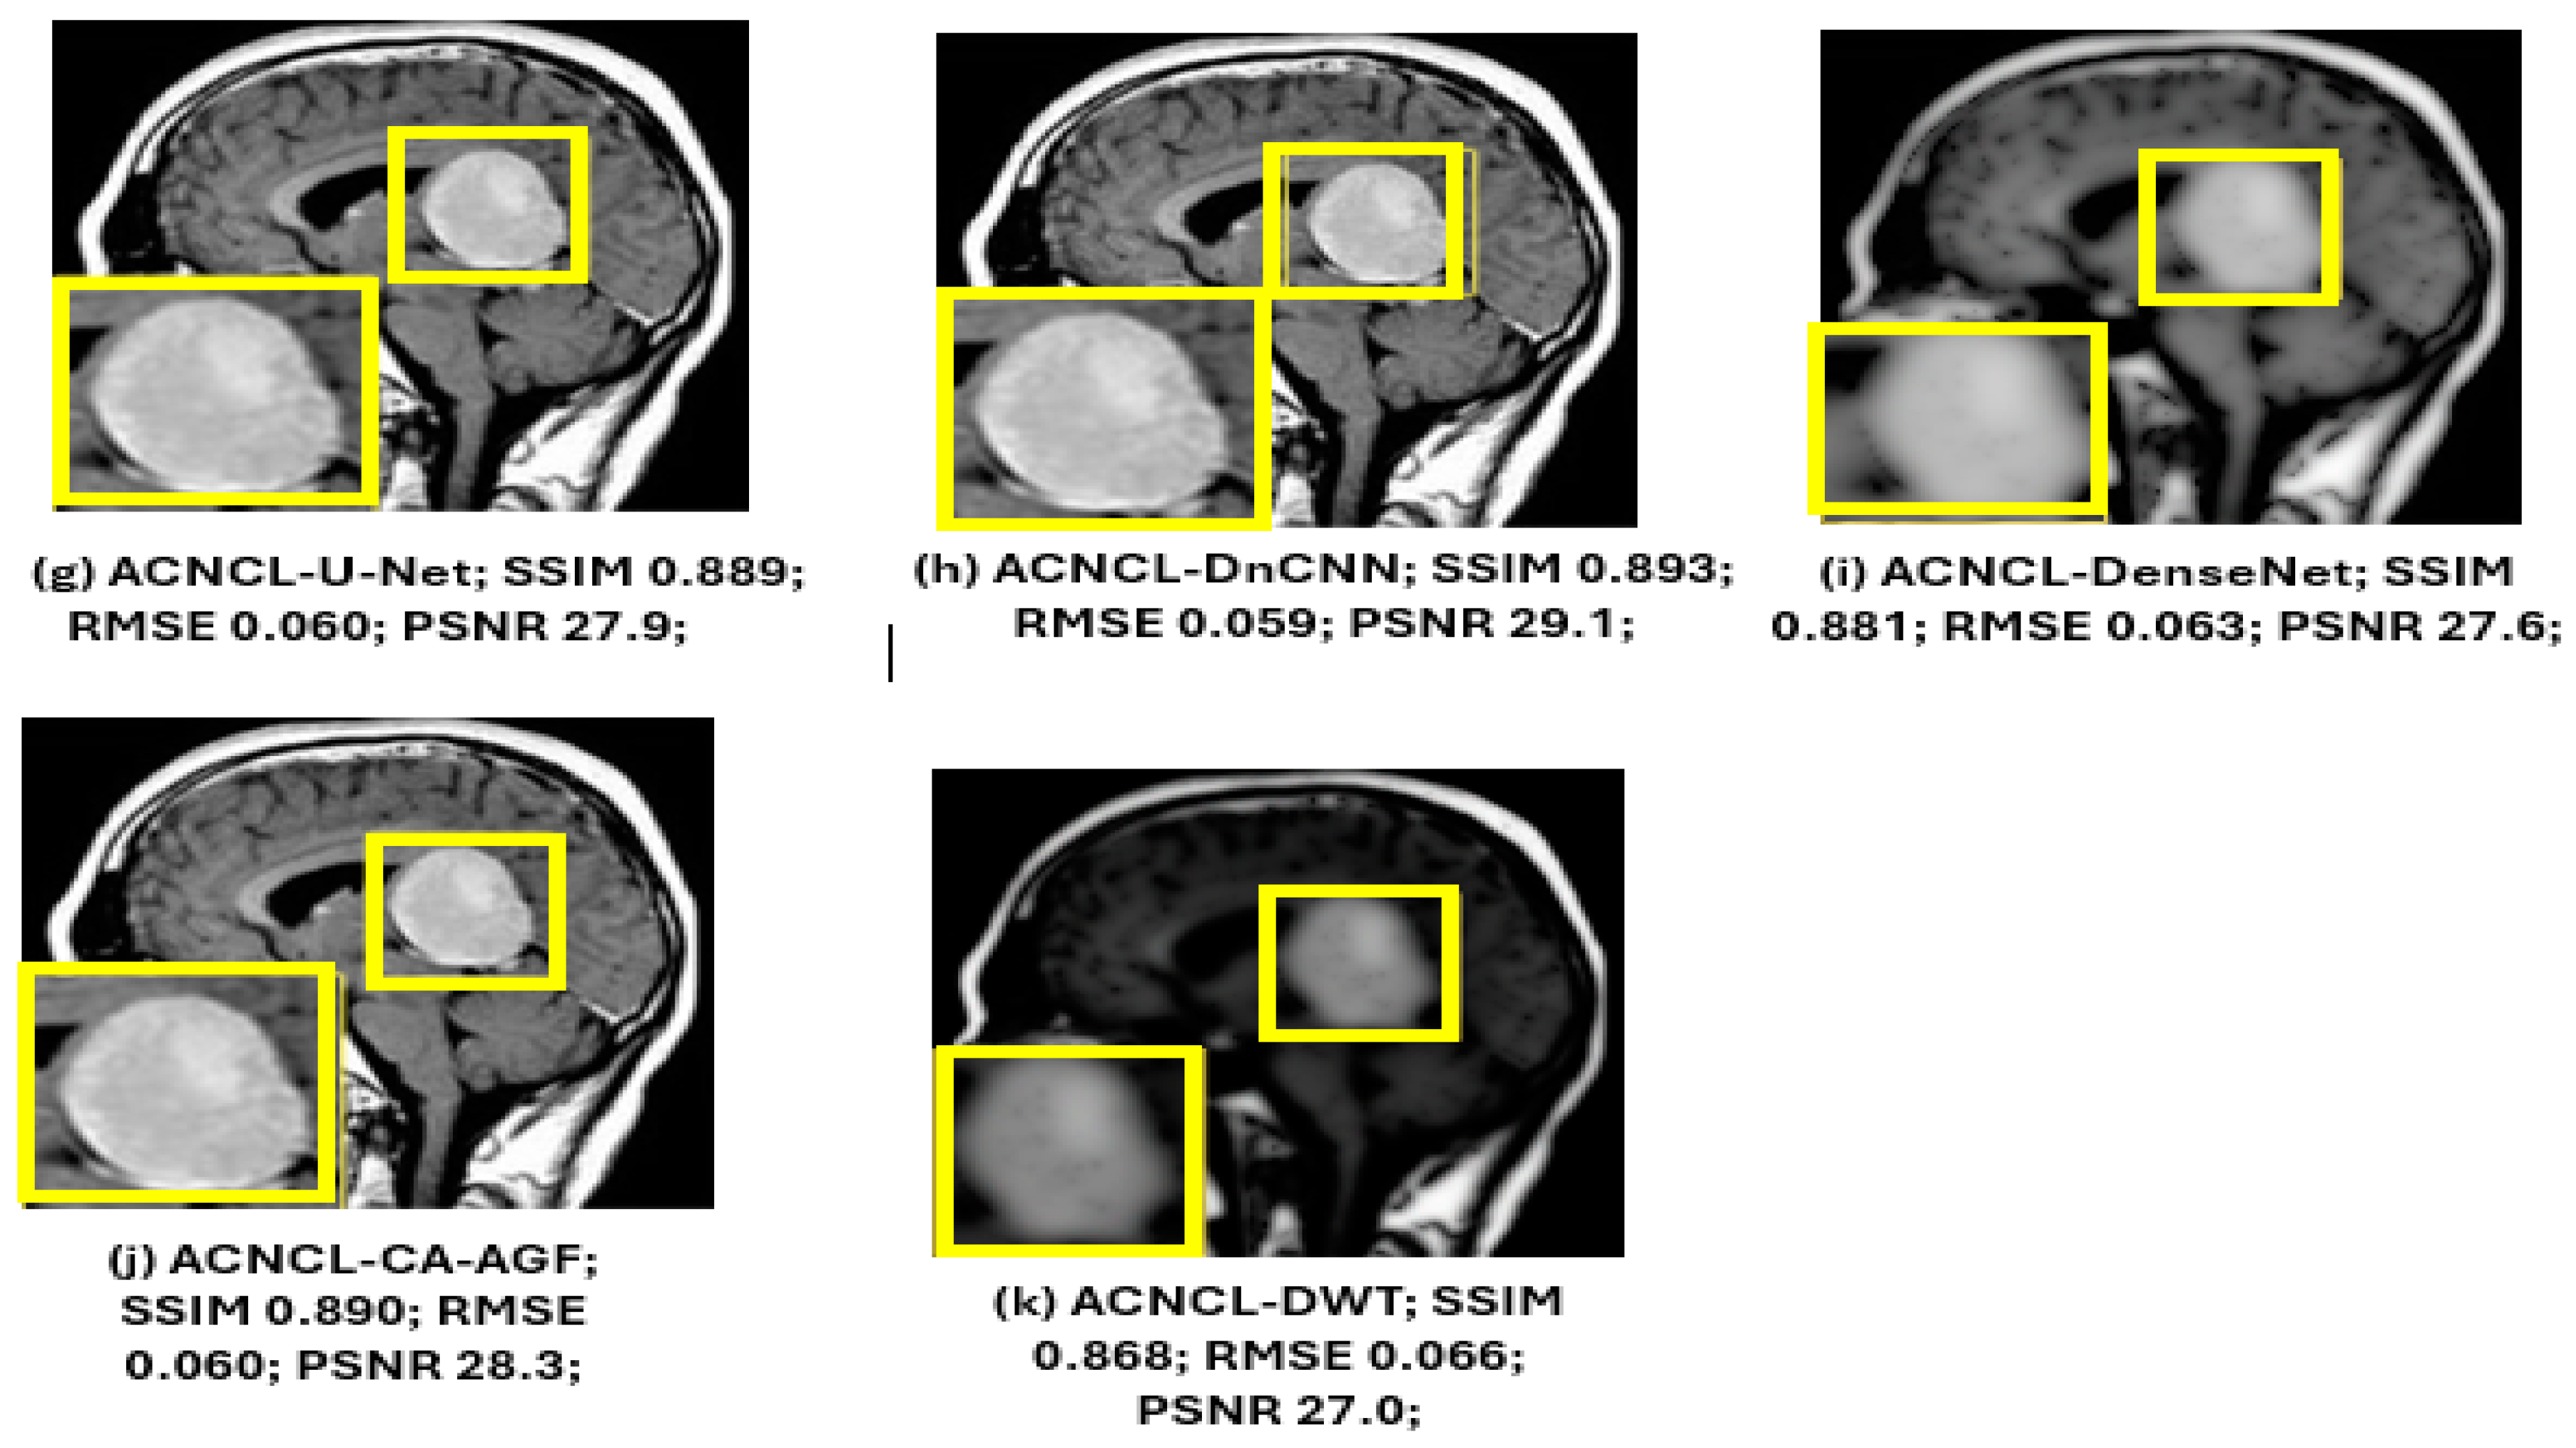

| ACNCL-U-Net | 0.889 ± 0.026 | 0.060 ± 0.005 | 27.9 ± 0.5 |

| ACNCL-DnCNN | 0.893 ± 0.025 | 0.059 ± 0.005 | 28.1 ± 0.5 |

| ACNCL-DenseNet | 0.881 ± 0.027 | 0.063 ± 0.005 | 27.6 ± 0.5 |

| ACNCL-CA-AGF | 0.890 ± 0.028 | 0.060 ± 0.005 | 28.3 ± 0.5 |

| ACNCL-DWT | 0.868 ± 0.029 | 0.066 ± 0.006 | 27.0 ± 0.5 |